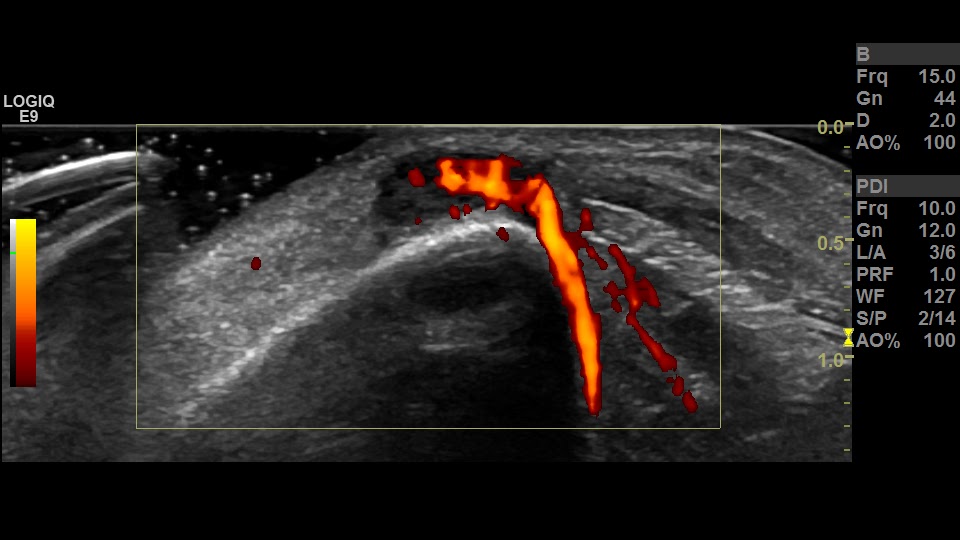

Power doppler and gray scale images in long axis at the left anterior shin show a vascularized, oval hypoechoic nodule along the cortex of the tibia.

I confess, I've never done US of an acute muscle hernia, but I have never seen much Doppler vascularity related to a muscle hernia. This is just wildly vascular.Just because a blob partially compresses and reduces through a fascial defect into the extensor compartment of the lower leg, can we be sure it's a muscle hernia?Can't there be a vascular mass (not muscle) that is doing the same?I would recommend MRI without and with contrast...would that be wrong?????

ReplyDeleteIt's an important thought and I don't think recommending an MRI would be wrong at all. I think a mass might be expected to invade through the muscular fascia but would be adherent and unlikely to freely herniate back and forth. The vascularity seems explainable by the episodic compression and release of the tissue stimulating perfusion although I agree that it is a lot. The nice thing about MSK ultrasound is that you can confirm the history directly with the patient and in this case it was pretty convincing for muscle herniation: sudden onset dull pain and lump with exertion, relieved with rest. Of course there are always zebra cases.....

ReplyDeleteThat's a good thought. I admit Dr. Umans comment made me worry that we were too quick to come down hard on muscle hernia! It's possible that MRI might show confusing mass-like abnormal signal at the site as well. The vascularity is greater than our other cases of muscle hernia but the "neck" of the fascia rent is small and I think the periodic compression and decompression of the muscle is stimulating that hyper-perfusion. The other cases that we've done--although also symptomatic--had much broader rents in the fascia. I think the history is pretty convincing (one of the things I love about MSK ultrasound, you can do a physical exam and history if you want to) and I have to believe that a mass would be more infiltrative and fixed across the fascia. Definitely thought provoking though.

ReplyDeleteIt looks like there is a big vessel that crossed the gap on your Power Doppler. I wonder if you had compressed right there for a few minutes if it would have made it go dusky...